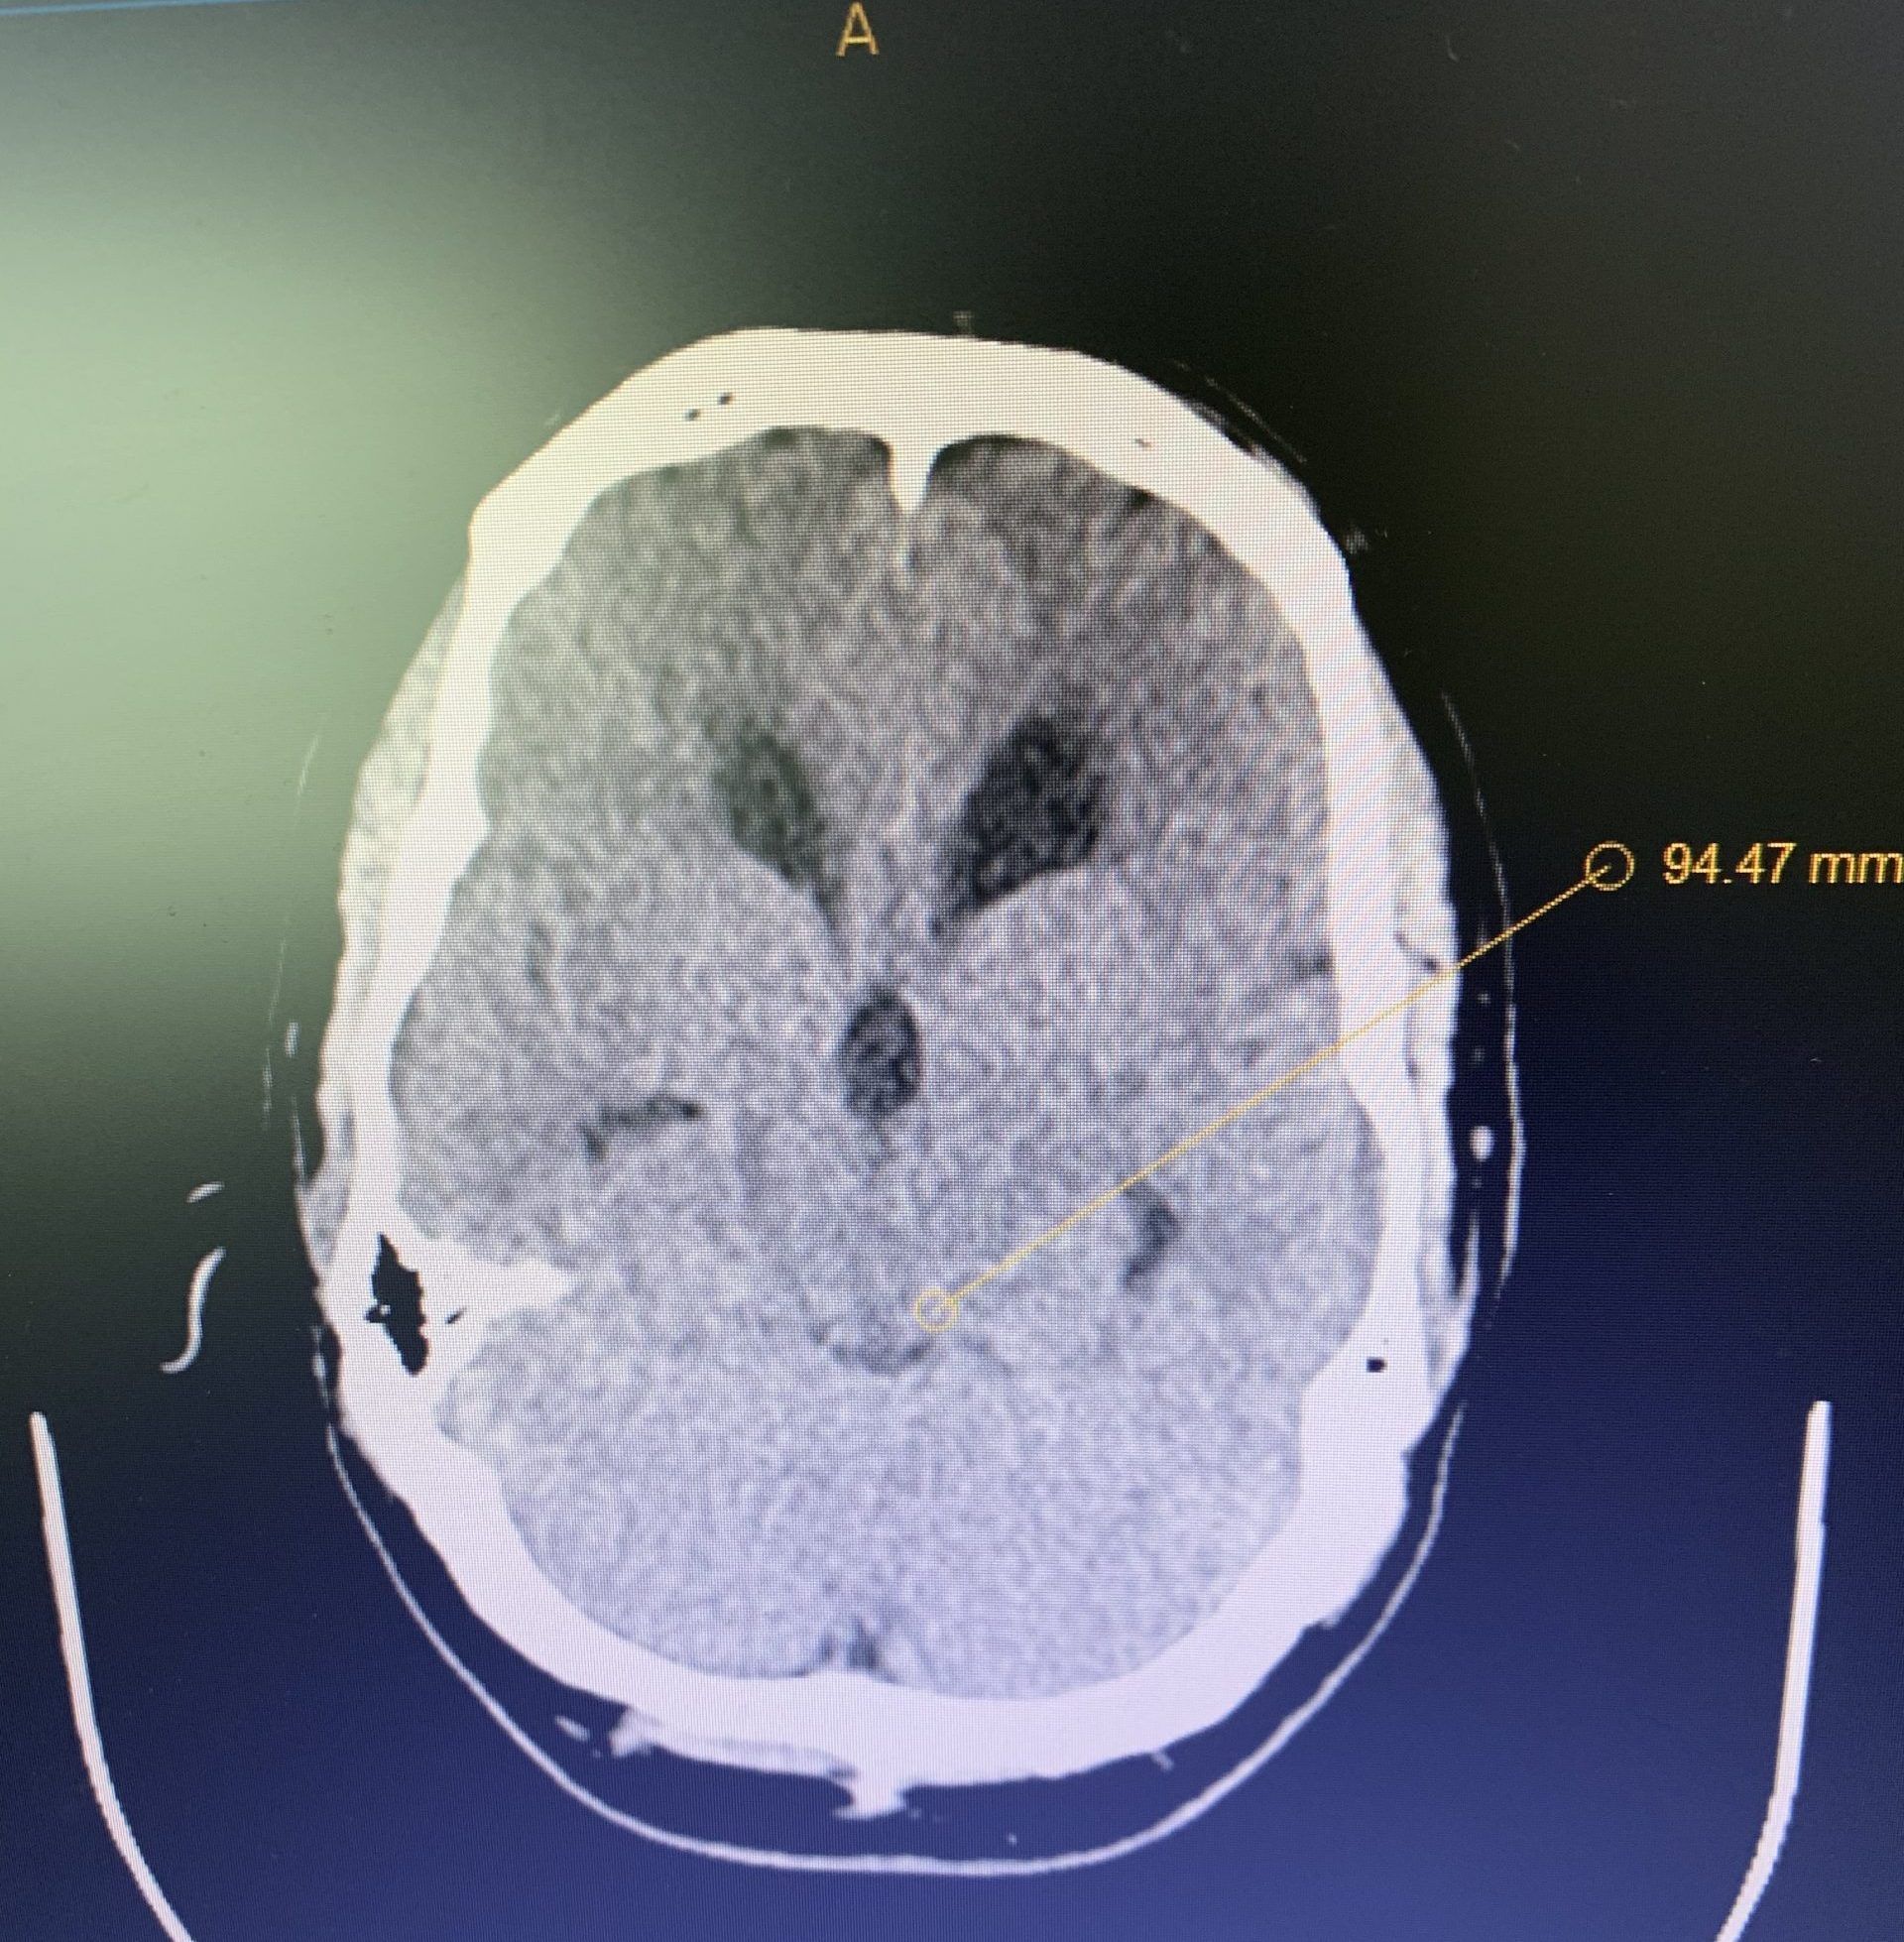

Imaging and other provocative diagnostic test showed the associated problems of Cranial Cervical Instability, incidental thoracic syringomyelia, Hashimoto Thyroidistis, Polycystic Ovarian Syndrome, Nutcracker Syndrome, Postural Orthostatic Hypotension, and Hypo/Hyper intracranial Pressure with spontaneous CSF leaks.

Thankfully, marked improvement of her brainstem and lower cranial nerve function, demonstrated on trial cervical traction improved with Cranial-Cervical Fusion.

Her symptoms of Intracranial hypotension have been challenging.